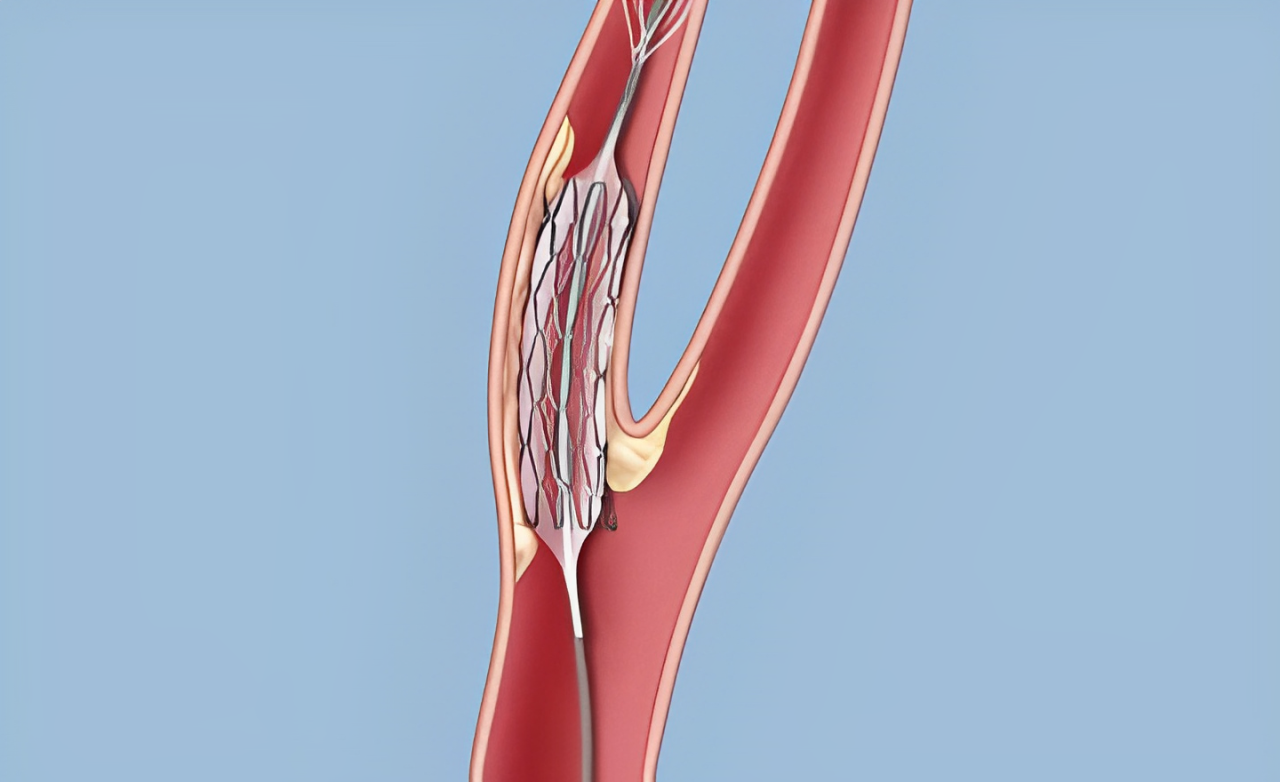

Narrowing of the carotid arteries due to plaque buildup, reducing brain blood flow and increasing risk of transient ischemic attacks.

Opens narrowed arteries supplying the brain, improving blood flow and reducing stroke risk through a precise, minimally invasive procedure.